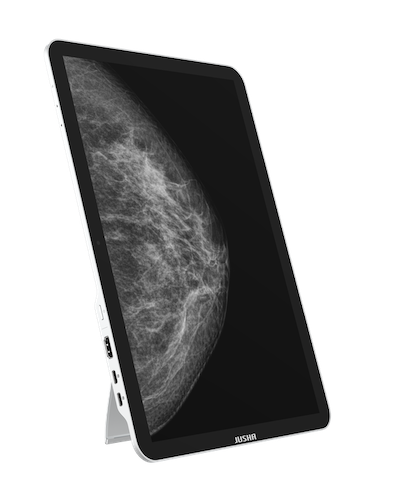

Představujeme přenosný diagnostický monitor JUSHA CP620G

Přenosný diagnostický monitor kalibrovaný pro datový formát DICOM.

Vaše jedinečné přenosné zobrazovací zařízení. Vyvinuto radiology pro lékaře a specialisty. |

CP620G nabízí zobrazení, analýzu a on-line práci se snímky kdykoli a kdekoli.

Model CP620G je přenosné zařízení mající certifikaci pro zobrazení snímků ve formátu DICOM |

Objevte práci s monitorem, který je větší než obyčejné tablety |

Pro ovládání a navigaci na dotykovém displeji velikosti 13,5" můžete použít své prsty, myš i klávesnici |

CP620G – to není jen další monitor

Je to 13,5" přenosný medicínský diagnostický monitor, navržený k zobrazování a analýze dat formátu DICOM, navíc doplněný o nezbytné funkce jako jsou: